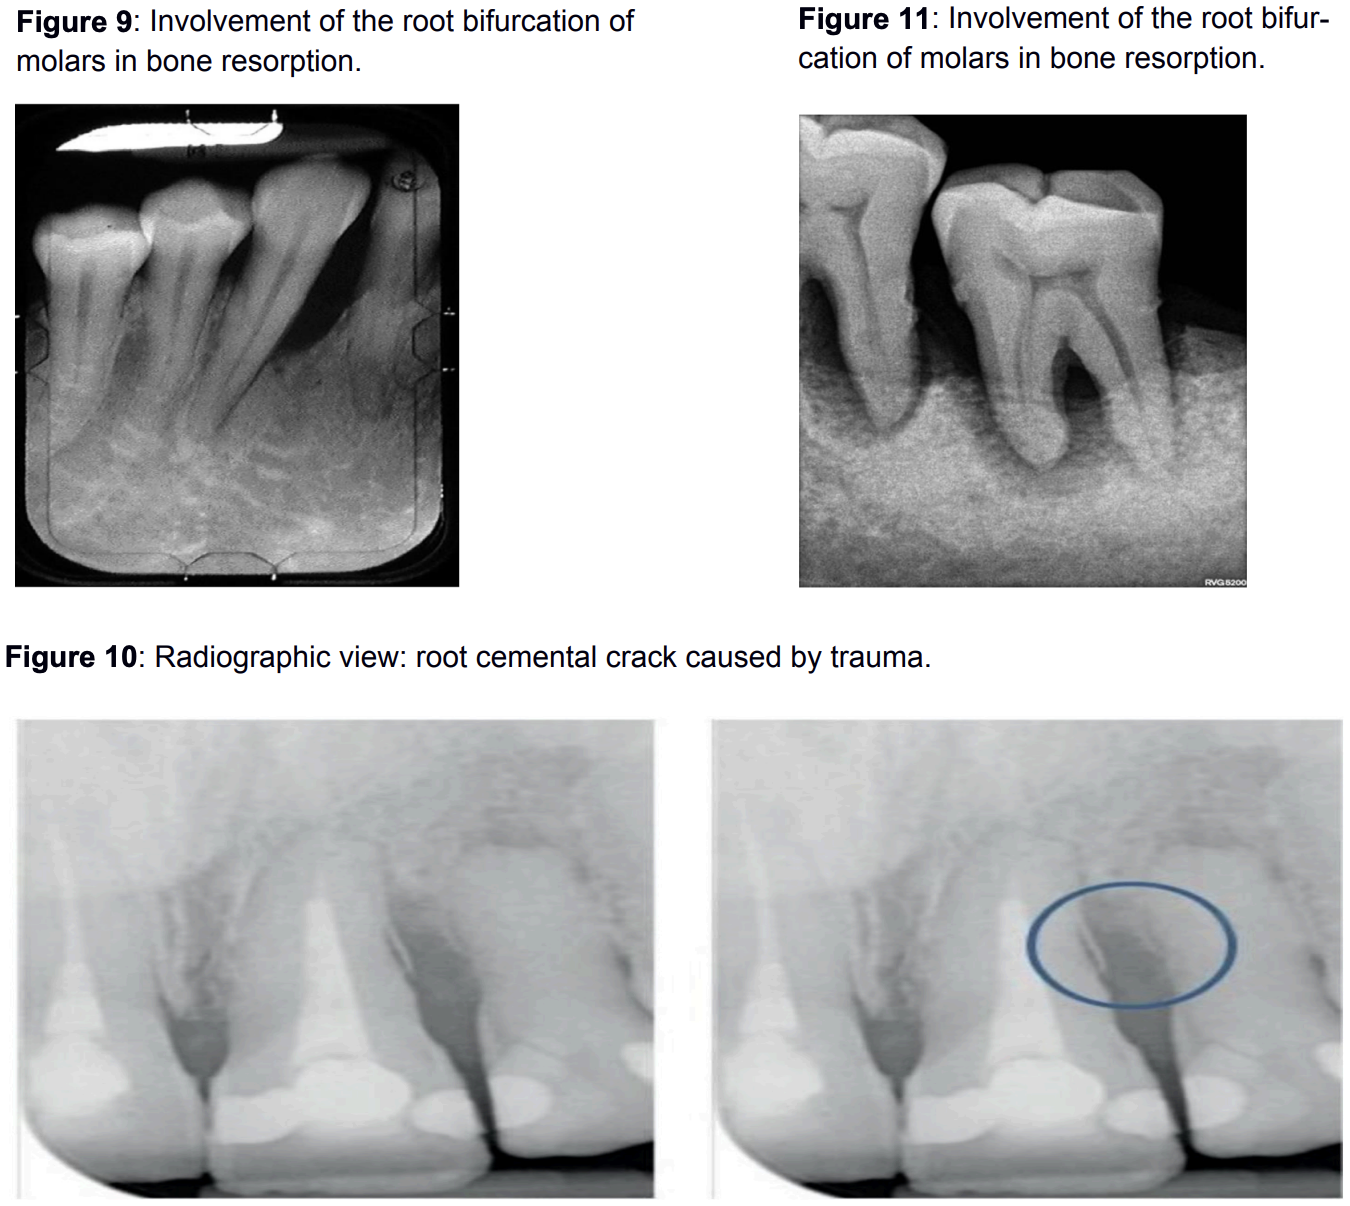

The periodontium cannot adapt when forces exceed its adaptive capabilities. Consequently, changes appear, such as an expansion of the coronal part of the periodontium in the form of a funnel, accompanied by bone resorption around the area. Bone resorption is most pronounced between the roots (furcations). Resorption of the root cementum also occurs. Clinically, these changes manifest as increased tooth mobility and pathological gingival sulcus depth.